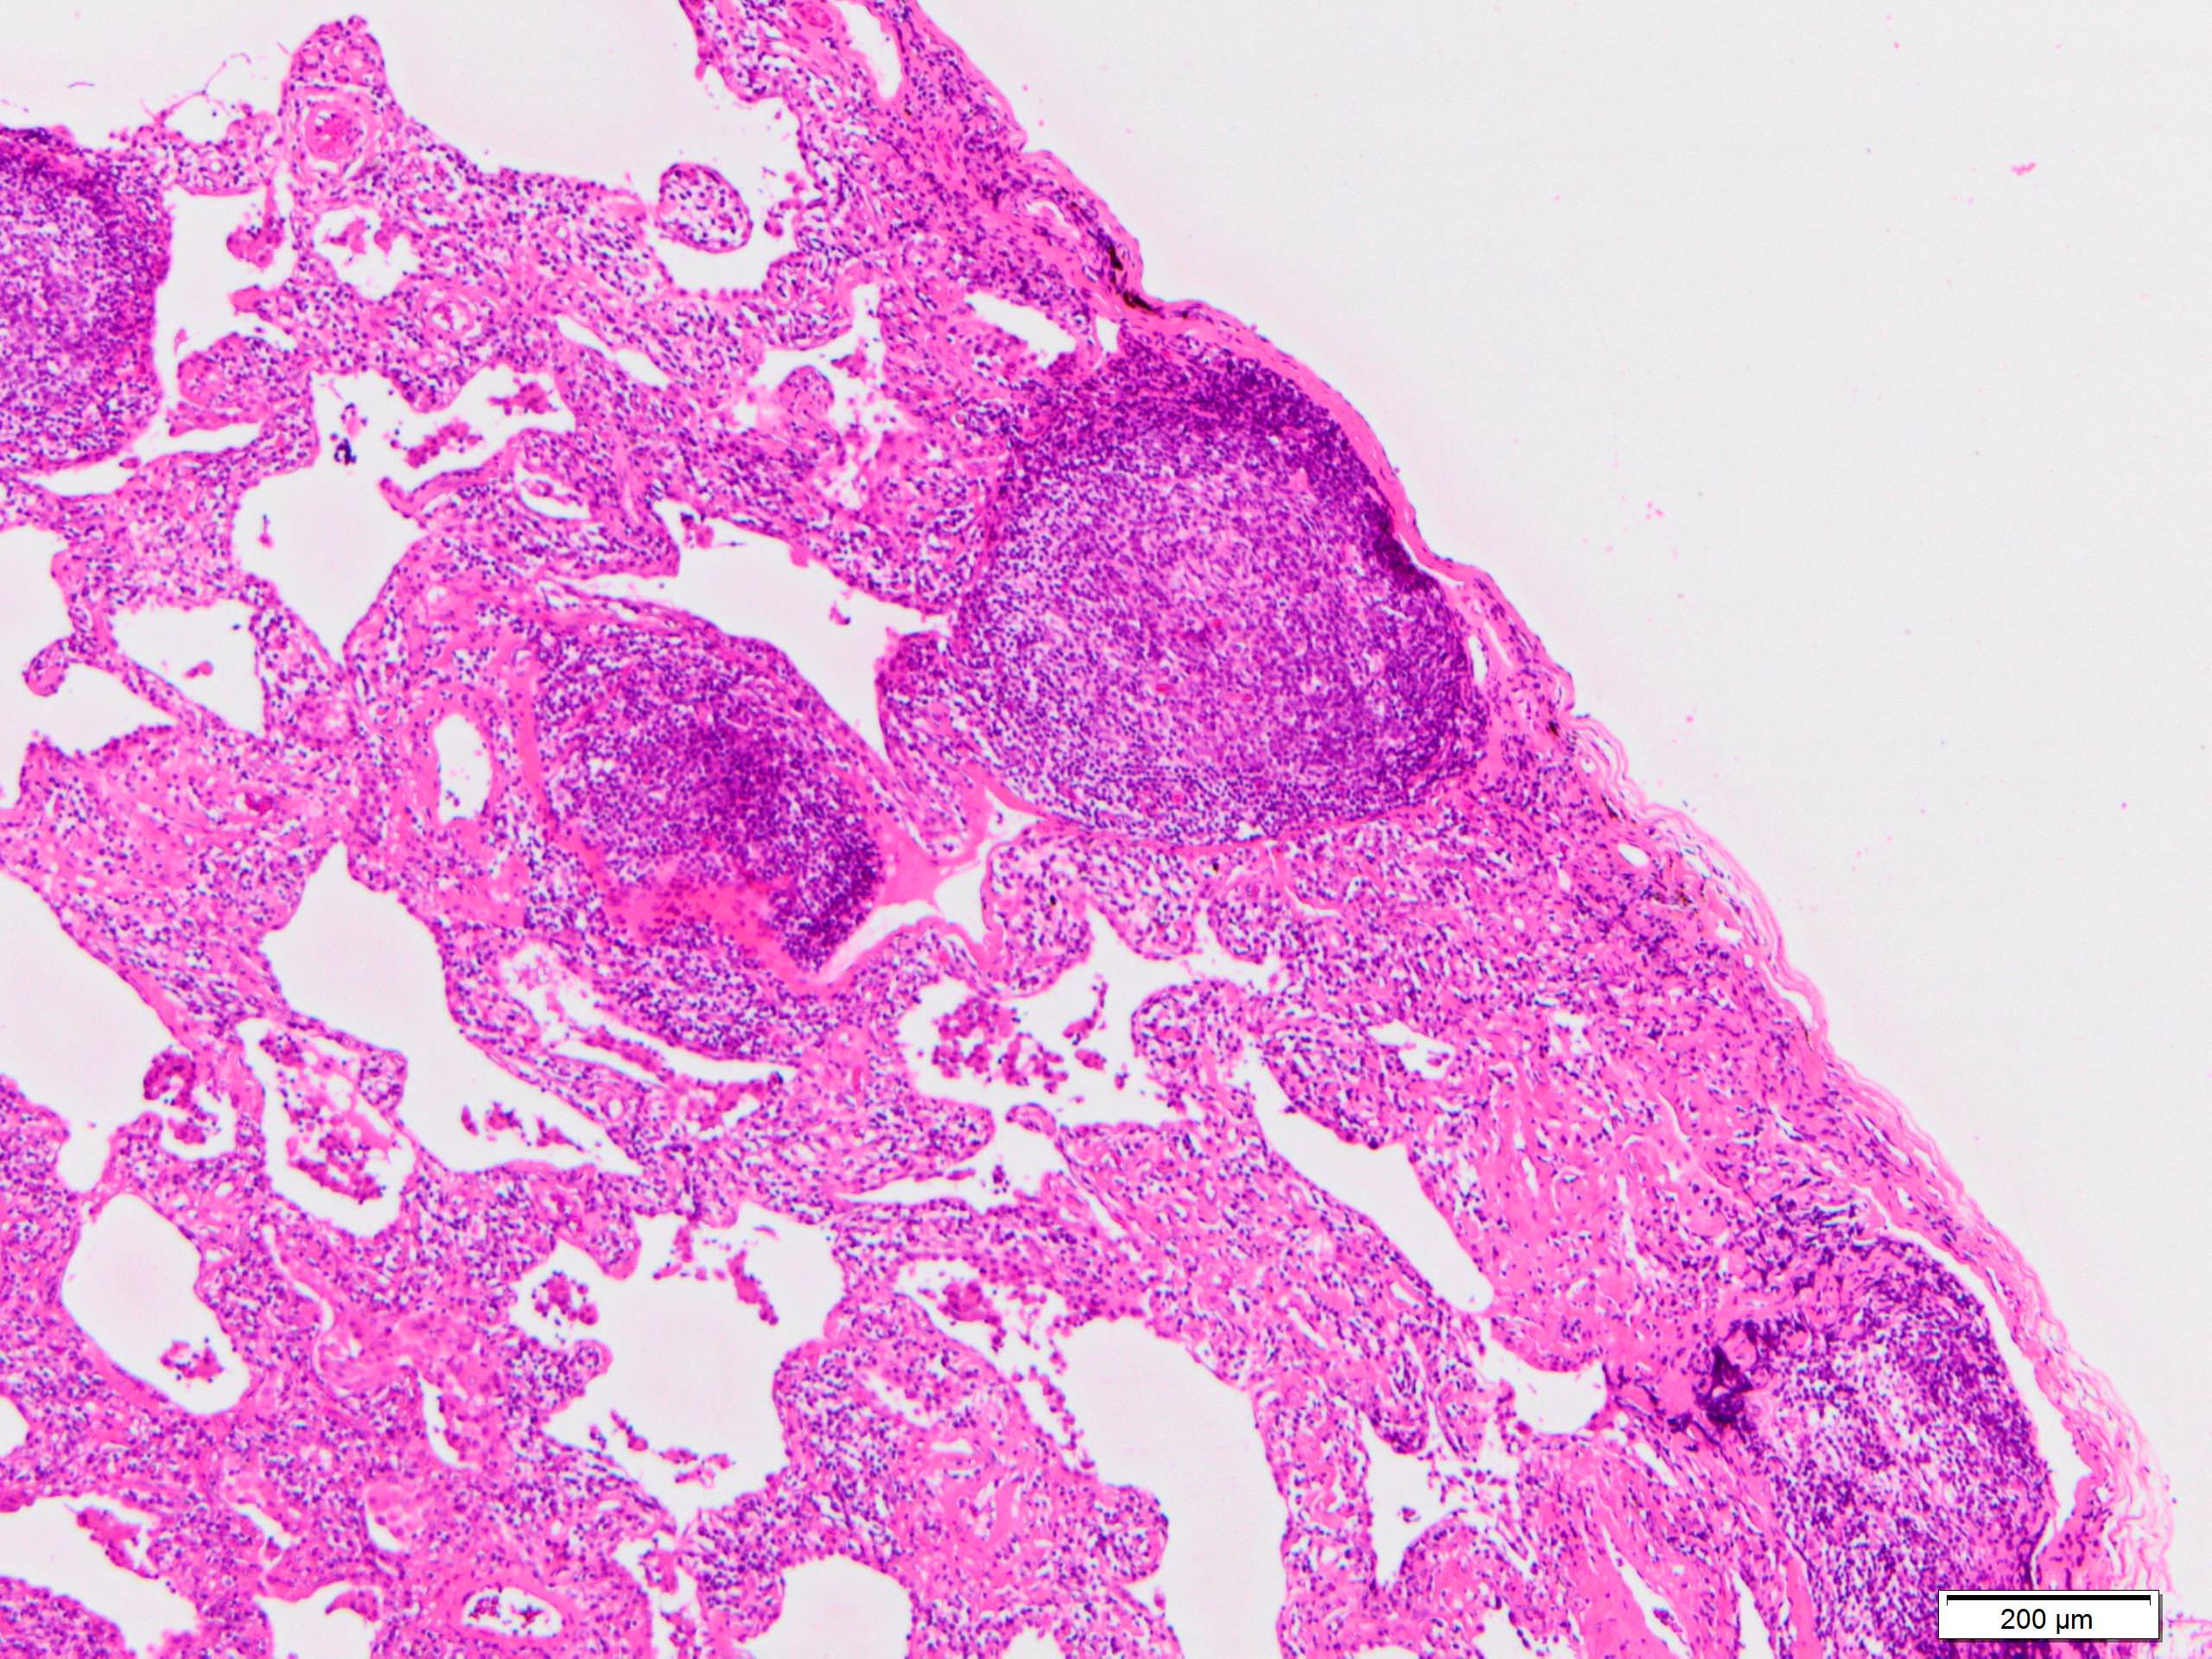

Microscopic (histologic) description

- Since there are few specific findings for NSIP pattern, it is essential to exclude other lung diseases on histology (Am J Respir Crit Care Med 2008;177:1338)

- Characteristic findings of NSIP pattern

- Diffuse and uniform inflammation ("temporal homogeneity") on low power of alveolar wall, bronchovascular bundles and pleura

- There are usually no normal alveolar walls in the affected lobules

- Cellular or fibrotic change

- Lymphocytic or plasmacytic infiltration

- Loose fibrosis

- Lung architecture is frequently preserved

- "Cellular NSIP" or "fibrotic NSIP" can be stated specifically in pathologist report

- Diffuse and uniform inflammation ("temporal homogeneity") on low power of alveolar wall, bronchovascular bundles and pleura

- Features of interstitial pneumonia with autoimmune features (IPAF) (Chest 2010;138:251):

- Lymphoid aggregates with germinal center

- Extensive pleuritis

- Prominent plasmacytic infiltration

- Dense perivascular collagen

Microscopic (histologic) images

Scroll to see all images.

Contributed by Akira Yoshikawa, M.D.

Images hosted on other servers:

Contributed by Akira Yoshikawa, M.D.

Images hosted on other servers: